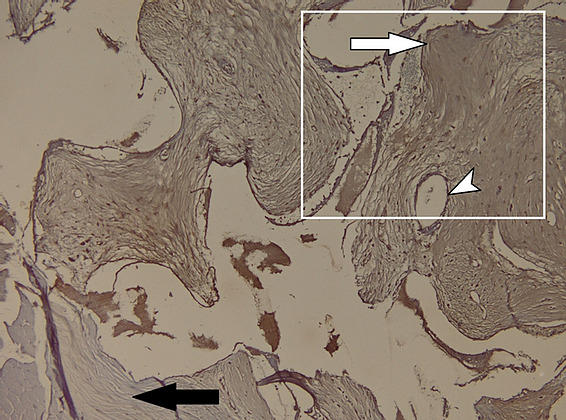

Figure 16: Microscopic appearance of the implant in HE X 200 staining. The presence of osteoclasts (white arrowhead) rich in mitochondria and with large nuclei – a sign of activity, at the interface with hydroxyapatite (black arrowhead) is noted.

Figure 17: Appearance of the hydroxyapatite implant in CD31 immunohistochemical staining. The presence of hydroxyapatite crystals at the level of the bone defect (black arrowheads) and osteoclasts – positive for CD31 (white arrowheads) is noted. As an internal control, the presence of vascular endothelium positive for CD31 (black arrows) is observed.